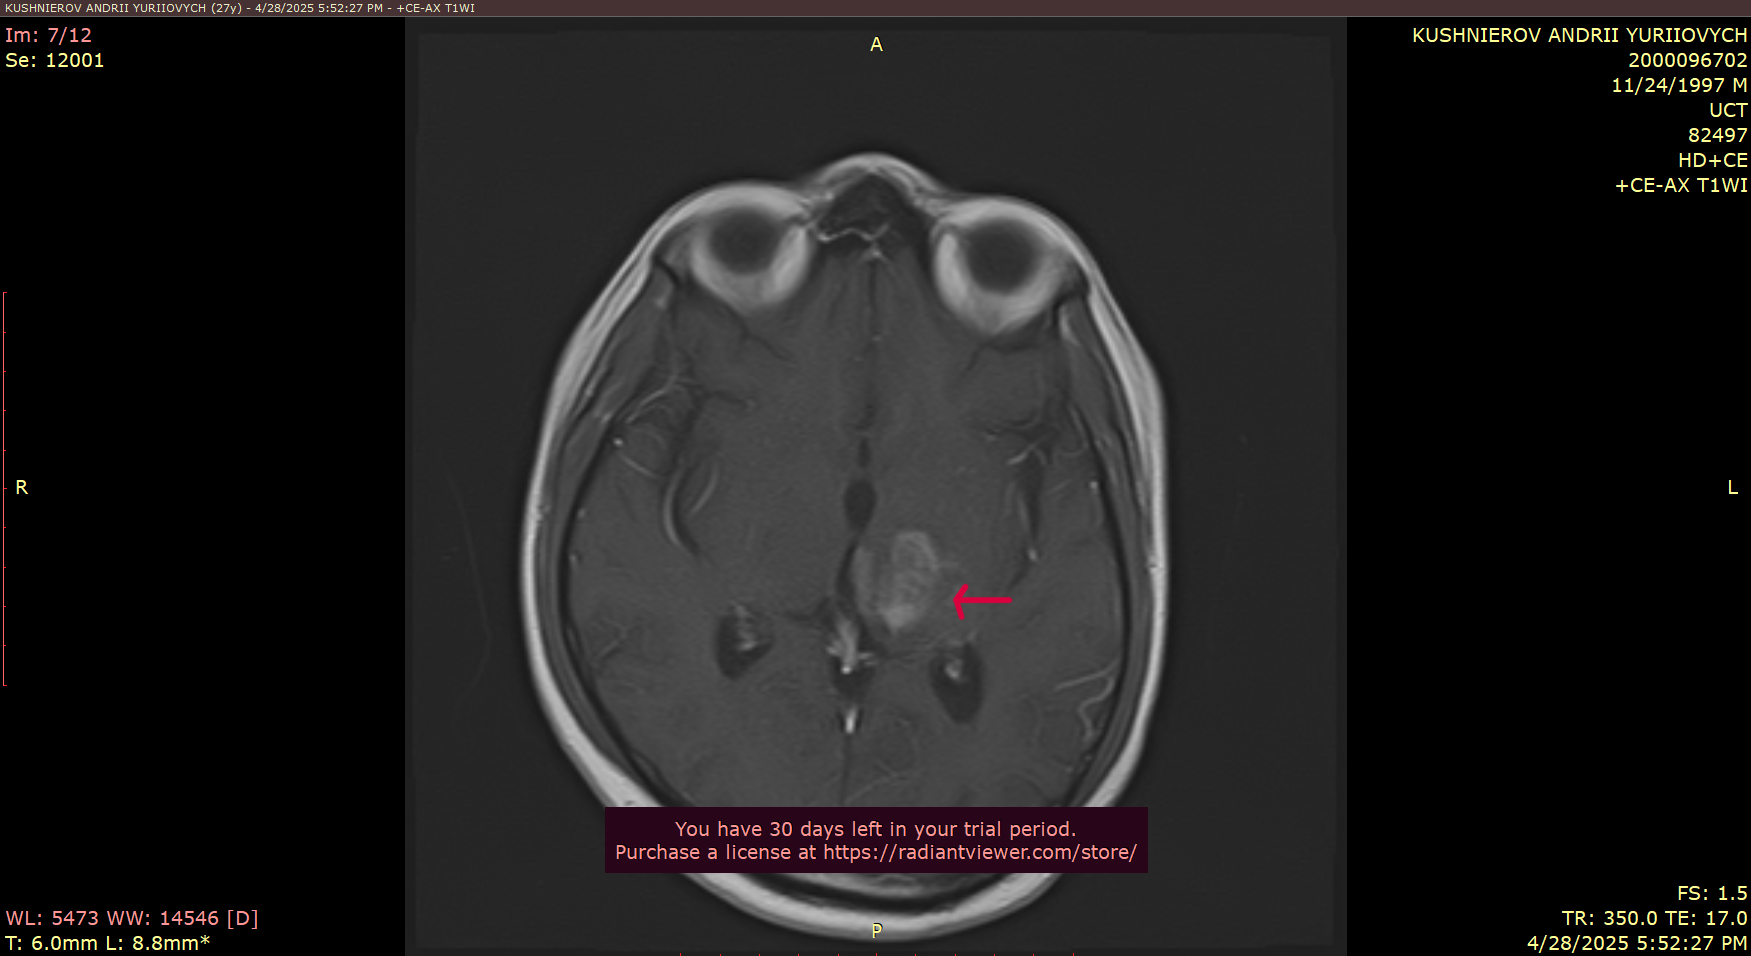

As some are aware - he was diagnosed last year with glioblastoma, an aggressive cancer of the brain and many in the community helped to fund his biopsy.

As many of you know, I’ve been battling glioblastoma — an aggressive form of brain cancer. Over the past year, I underwent 12 months of chemotherapy, hoping it would stop the tumor’s growth. Unfortunately, it hasn’t helped. The situation has become critical.

The location of the tumor in the brain makes the tumor almost inoperable, because of the high risk of being paralyzed — but now my condition has worsened, and emergency brain surgery must be done very soon, likely next week, here in Ukraine to address the immediate threat. This surgery won’t heal me, but it’s necessary to stabilize my condition. After that, I must travel to Germany for more advanced treatment and another surgery, which may allow doctors to remove a larger portion of the tumor and offer a better chance at extending my life.

Description of MRI scan results. Scan images are included above.